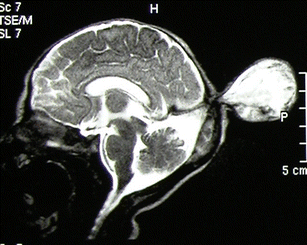

Levitsky DB, Mack LA, Nyberg DA, Shurtleff DB, Shields LA, Nghiem HV, Cyr DR (1995) Fetal aqueductal stenosis diagnosed sonographically: how grave is the prognosis? AJR Am J Roentgenol 164:725–730

Renier D, Saint-Rose C, Pierre-Kahn A, Hirsch JF (1988) Prenatal hydrocephalus: outcome and prognosis. Child’s Nerv Syst 4:213–222

Senat MV, Bernard JP, Delezoidë A, Saugier-Veber P, Hillion Y, Roume J, Ville Y (2001) Prenatal diagnosis of hydrocephalus-stenosis of the aqueduct of Sylvius by ultrasound in the first trimester of pregnancy. Report of two cases. Prenat Diagn 21:1129–1132